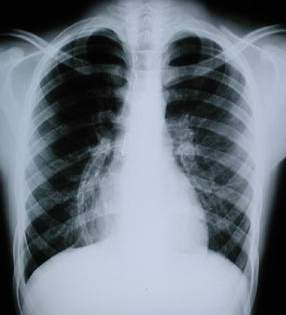

Radiología Pos – Operatoria

La radiografía anteroposterior del tórax, pos-operatorio 72 horas: muestra un corazón en posición central, el mediastino centrado la ausencia de neumotórax o derrame pleural, el material de síintesis esternal (alambre). El drenaje aspirativo circular precostal.

La Rx lateral Izquierda del tórax muestra: la osteosintesis a nivel del 2 arco, la rectificación esternal, con la disminución del espacio retroesternal y el aumento del diámetro de la base del tórax en su extremo inferior.

Rx post extubacion endotraqueal